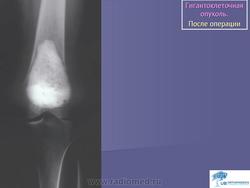

Гигантоклеточная опухоль.